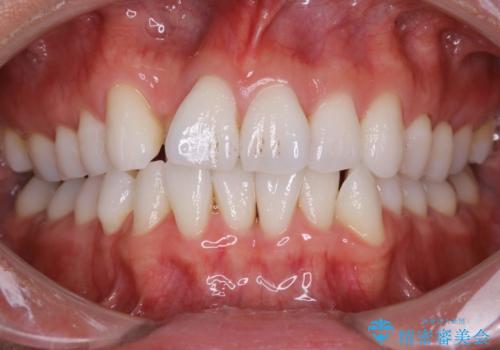

内側に入ってしまった前歯を正しい位置へ インビザライン矯正

右上の前から2番目の歯が引っ込んで、下の前歯にはガタガタがありました。

上下の歯と歯の間を少量ずつ削りスペースを作り、インビザラインにて並べる計画としました。

目立たずに矯正治療を終えることができたことに満足していただけました。